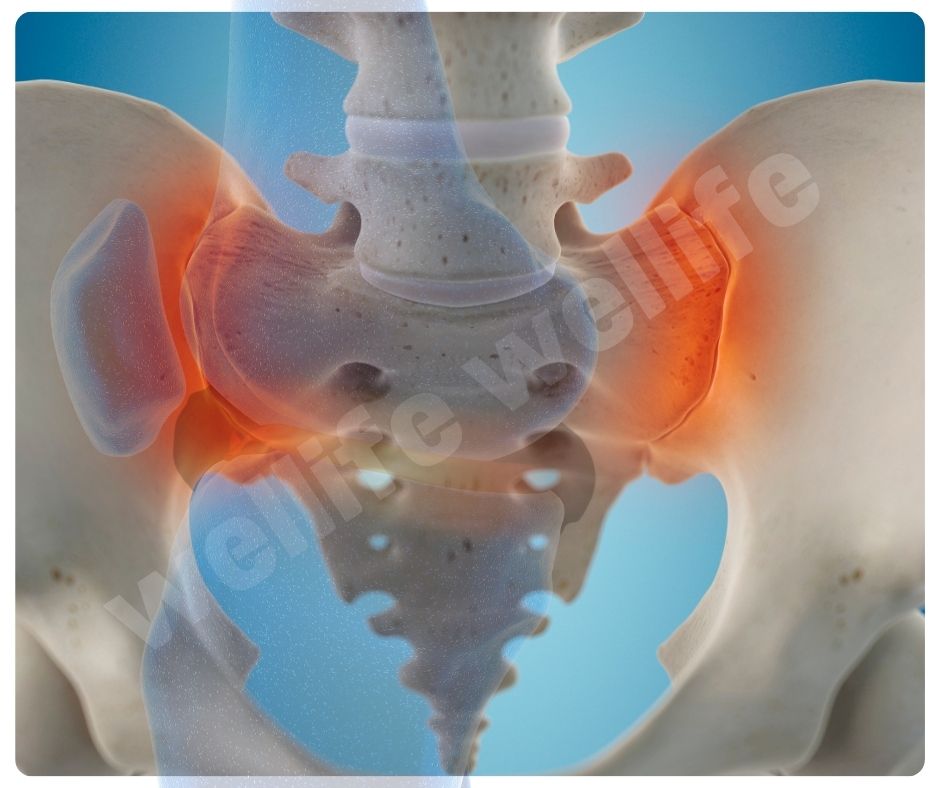

콘드로이친 효능 중 가장 대표적인 것은 골관절염(Osteoarthritis) 완화입니다. 골관절염은 연골이 닳아 없어지면서 통증과 강직을 유발하는 만성 질환인데요, 콘드로이친은 연골 손상을 줄이고 증상을 완화하는 데 효과적이에요.

- 연골 보호 및 재생: 콘드로이친은 연골의 구조를 유지하고, 손상된 연골의 재생을 돕는 효능이 있습니다.

- 통증 완화: 관절 통증을 줄이고, 관절의 기능을 개선하는 데 도움을 줍니다.